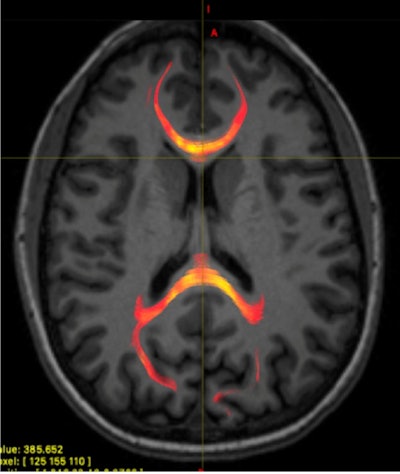

More specifically, the MR images show how the corpus callosum, which contains nerve fibers that carry signals between the brain's left and right hemispheres, is vulnerable to damage from a mild traumatic brain injury. When the concussion occurs, it disrupts the signals between the brain's two hemispheres.

"Looking at how water molecules are diffusing in the nerve fibers in the corpus callosum and within the microenvironment around the nerve fibers allows us to better understand the white matter microstructural injury that occurs," said study co-author Dr. Melanie Wegener, resident physician at NYU Langone Health.

Most importantly, reaction time results among the healthy controls corresponded with several diffusion measures in the splenium, an area of the corpus callosum located between the right visual cortex and the left language center. There was no such correlation in the patients with concussions, which would suggest microstructural changes occurred because of the concussions.